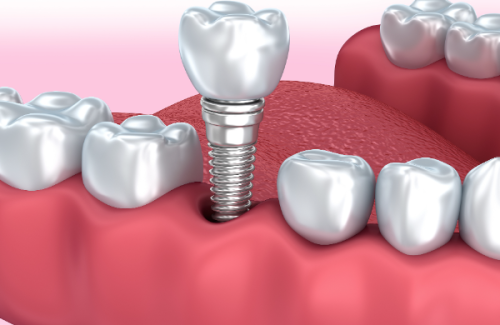

种植体

种植体的价格差异比较大。国产种植体通常在5000 - 10000元,而进口种植体,像瑞士、瑞典的品牌,价格约为10000 - 20000元。一般来说,进口种植体在质量和稳定性上可能更有优势,但价格也相对较高。如果你的预算有限,国产种植体也是一个不错的选择。